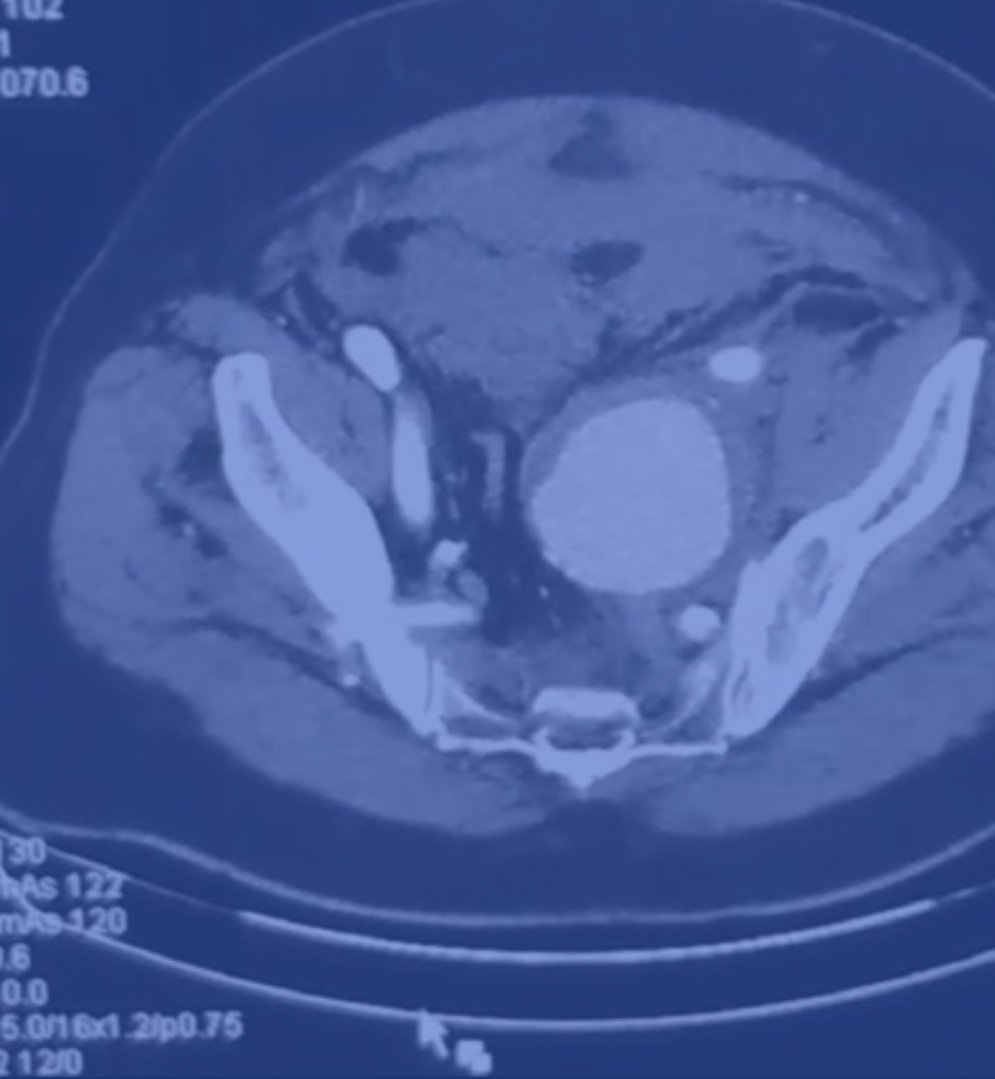

Τι είναι το ανεύρυσμα λαγονίου αρτηρίας;

Πόσο συχνά είναι τα ανευρύσματα των λαγονίων αρτηριών;